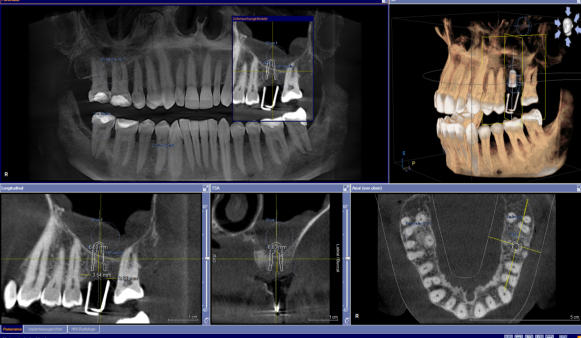

Die 3D-Röntgentechnik oder digitale Volumentomographie liefert 3-dimensionale Ansichten der Kiefer und der Zähne und ist ein großer Gewinn für die zahnärztliche Diagnostik. Bestimmte krankhafte Prozesse werden nur mit diesem Verfahren dargestellt. Häufig werden auch bisher versteckte Befunde entdeckt. Implantatplanungen können mit 3D-Röntgenaufnahmen präziser und vor allem sicherer vorgenommen werden. Exakte Vermessungen sind in diesen Ansichten möglich. Wurzelbehandlung (Endodontie) lassen sich sicher durchführen. Die 3D-Technik ermöglicht ein exaktes Erkennen der Wurzelanatomie, Lokalisieren und Vermessen der Wurzelkanäle. Parodontalbehandlungen (regenerative Parodontologie) lassen sich im Voraus planen. Dadurch kann die Behandlung gezielt und schonend durchgeführt werden. Weitere diagnostische Anwendungsgebiete der digitalen Volumentomographie liegen im Bereich der zahnärztlichen Chirurgie, z.B. für schwierige Weisheitszahnentfernungen, Lagebestimmungen von verlagerten Zähnen und Fremdkörpern.

Die 3D-Röntgentechnik oder digitale Volumentomographie liefert 3- dimensionale Ansichten der Kiefer und der Zähne und ist ein großer Gewinn für die zahnärztliche Diagnostik. Bestimmte krankhafte Prozesse werden nur mit diesem Verfahren dargestellt. Häufig werden auch bisher versteckte Befunde entdeckt. Implantatplanungen können mit 3D-Röntgenaufnahmen präziser und vor allem sicherer vorgenommen werden. Exakte Vermessungen sind in diesen Ansichten möglich. Wurzelbehandlung (Endodontie) lassen sich sicher durchführen. Die 3D- Technik ermöglicht ein exaktes Erkennen der Wurzelanatomie, Lokalisieren und Vermessen der Wurzelkanäle. Parodontalbehandlungen (regenerative Parodontologie) lassen sich im Voraus planen. Dadurch kann die Behandlung gezielt und schonend durchgeführt werden. Weitere diagnostische Anwendungsgebiete der digitalen Volumentomographie liegen im Bereich der zahnärztlichen Chirurgie, z.B. für schwierige Weisheitszahnentfernungen, Lagebestimmungen von verlagerten Zähnen und Fremdkörpern.